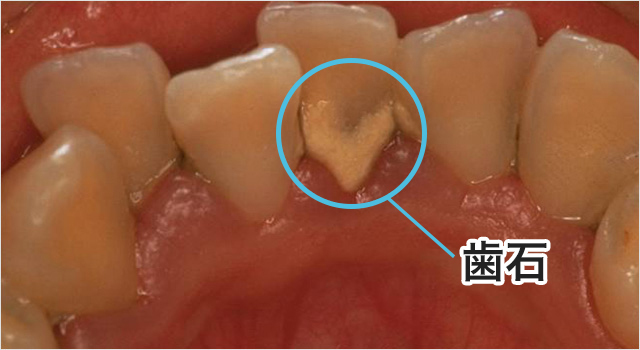

歯医者 歯石取り 頻度- スケーリングは歯医者さんで安全にできる「歯石取り」のことです。 歯石とは、前歯の裏側 や奥歯の側面などに できやすい 乳白色の石 のような硬い汚れ のことです。どんな人にもできる可能性があります。歯石は、歯の表面に付着した歯垢(プラーク)が歯石は歯医者さんで除去してもらうことができますが、どのくらいの頻度で取ったほうが良いのでしょうか。 今回は歯医者での歯石取りを行う頻度について解説します。 歯石とは? 歯石は、歯に溜まった「歯垢」が石灰化したものです。

歯石を取りに、どれくらいの頻度で歯医者さんに行けばいいのですか? 虫歯とはどのような病気ですか? なぜ虫歯ができるのですか? 虫歯にならない友人がいますが、なぜ虫歯にならないのですか? 虫歯ができやすい場所はありますか? 絶対歯石を取ったほうがいい本当の理由 なぜ歯石を取らなくてはいけないのかと思っている方も多いのではないでしょうか。 歯石とは歯の周りについている石のようなものです。 歯医者で歯石を取るのは面倒ですよね。 しかし、実は歯石はただの石で 普段のブラッシングで落とせないため、定期的に歯科医院で診てもらい歯石取りを行うようにしましょう。 歯周病が原因歯石取りのデメリット3選 一般的に言われる、歯石取りのデメリットを3つ紹介します。 痛みが出る;